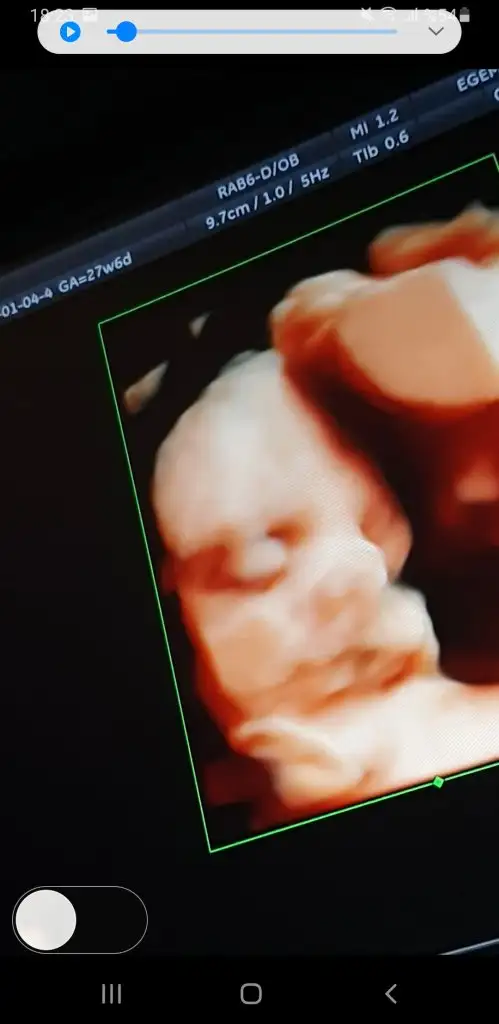

Kızlar iyi akşamlar, biraz önce kontrolden geldim, sat a göre 27+6 ama ultrasonda 27+4 çıktı, bebeğim 1120 gr - 36 cm olmuş🥰 rahim ağzı uzunluğum 4 cm üzeri çıktı.

Herşey yolunda gidiyor çok şükür, inşallah hiçbir problem çıkmadan hepimiz sağlıcakla doğururuz🙏

Video çekmiştim ondan kareler aldım😍

Her dururuşu bebeği değiştiriyor.

Screenshot_20230104-182322_Photos.jpg Screenshot_20230104-182558_Photos.jpg Screenshot_20230104-181937_Photos.jpg